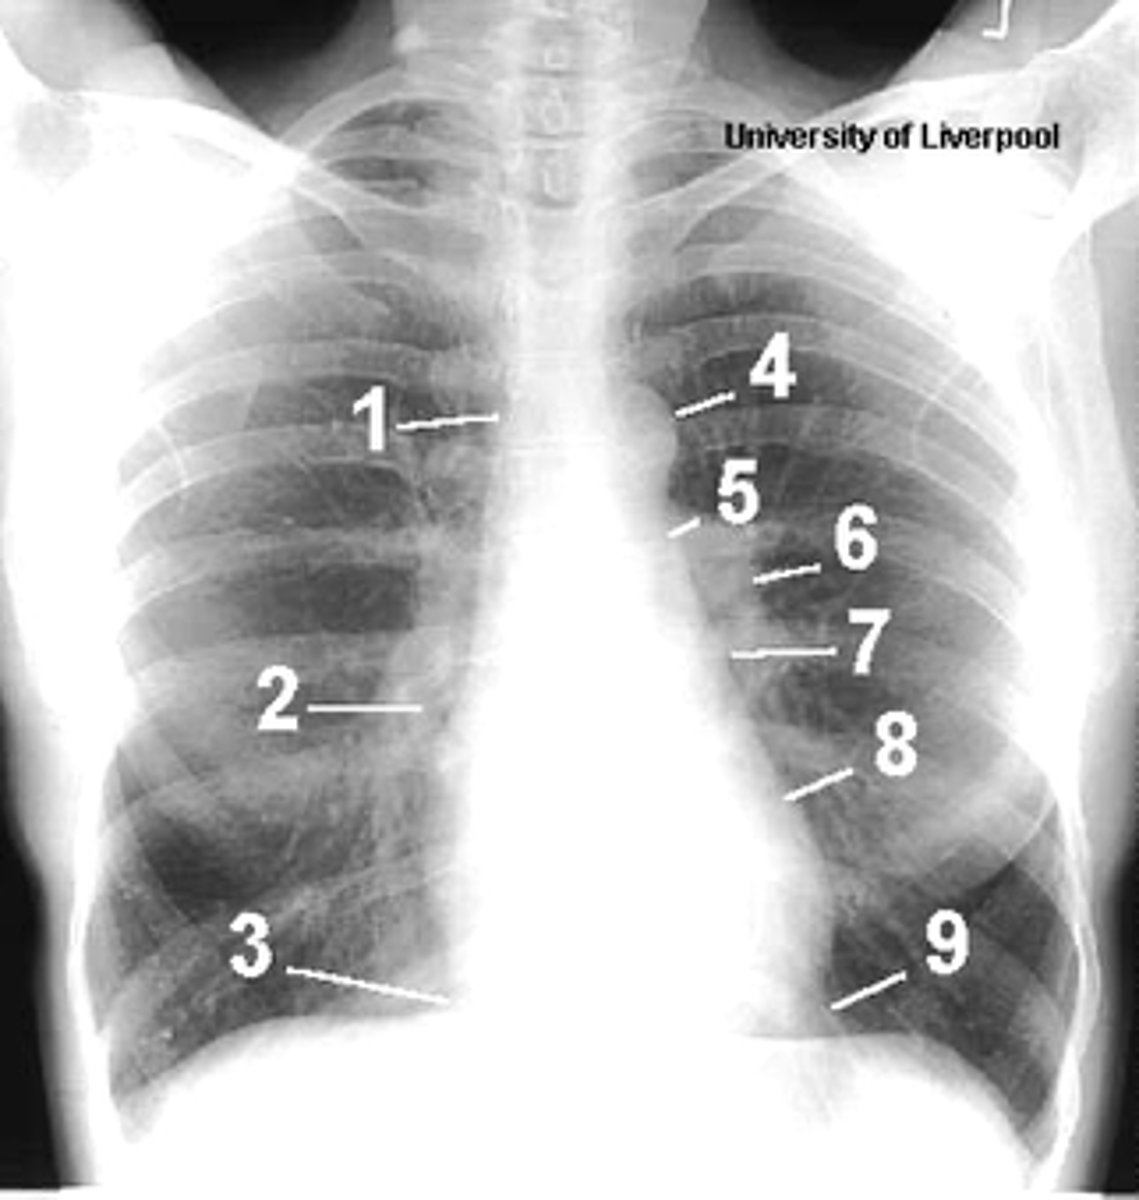

1

superior vena cava

2

right atrium

3

inferior vena cava

4

aortic arch or knob

5

left pulmonary trunk

6

left pulmonary artery

7

left atrium

8

left ventricle

9

left cardiophrenic angle